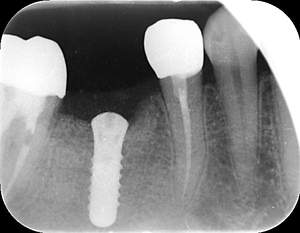

インプラント治療の症例3

レントゲン写真

- Befor

- After

| 年齢 | 50代・男性 |

|---|---|

| 主訴 | 左下7番 |

| 治療内容 | 右下7番インプラント埋入 |

| 治療費 | 合計:572,000円 診断料:55,000円 埋入料:165,000円 サージカルガイド:55,000円 静脈内鎮静麻酔:77,000円 仮歯:55,000円 上部構造(フルジルコニア):165,000円 (2023年1月現在) |

| 治療期間 | 約8ヶ月 |

| 治療方針 | 骨が十分にあるため、骨造成をすることなく埋入した。かみ合わせが強いので、負荷がかからないよう、夜寝るときにマウスピースをつけるよう指示をした。 |

| 担当者所見 | 左下6番7番のインプラントは他院で埋入しており、右下7番は抜歯したままで、かみ合わせの歯が落ちてきてしまうのでインプラントを埋入しました。 |